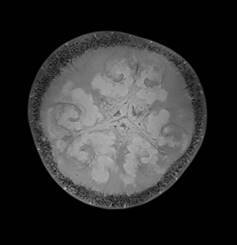

MRT-Aufnahmen eines Apfels

MRT-Aufnahmen von Apfel und Melone